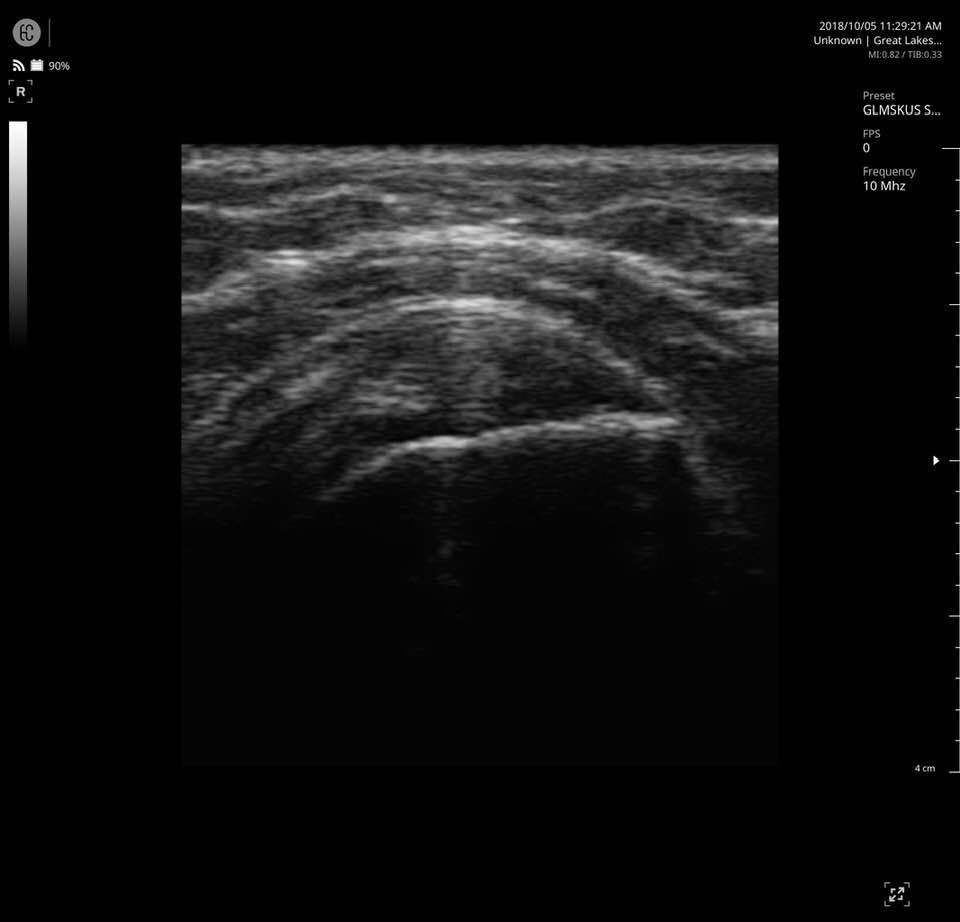

The SONON 300L transducer has cutting-edge technology and its software, combined with a proprietary sensor, turns any mobile device into a mobile ultrasound monitor with the same image quality and knobology as a traditional US machine. Software includes individual preset settings for your most common test.

- MSK

Specifications for SONON 300L:

- Multi-frequency: 5MHz 7.5MHz 10MHz

- Depth: max 10cm

- Field of View: 40mm